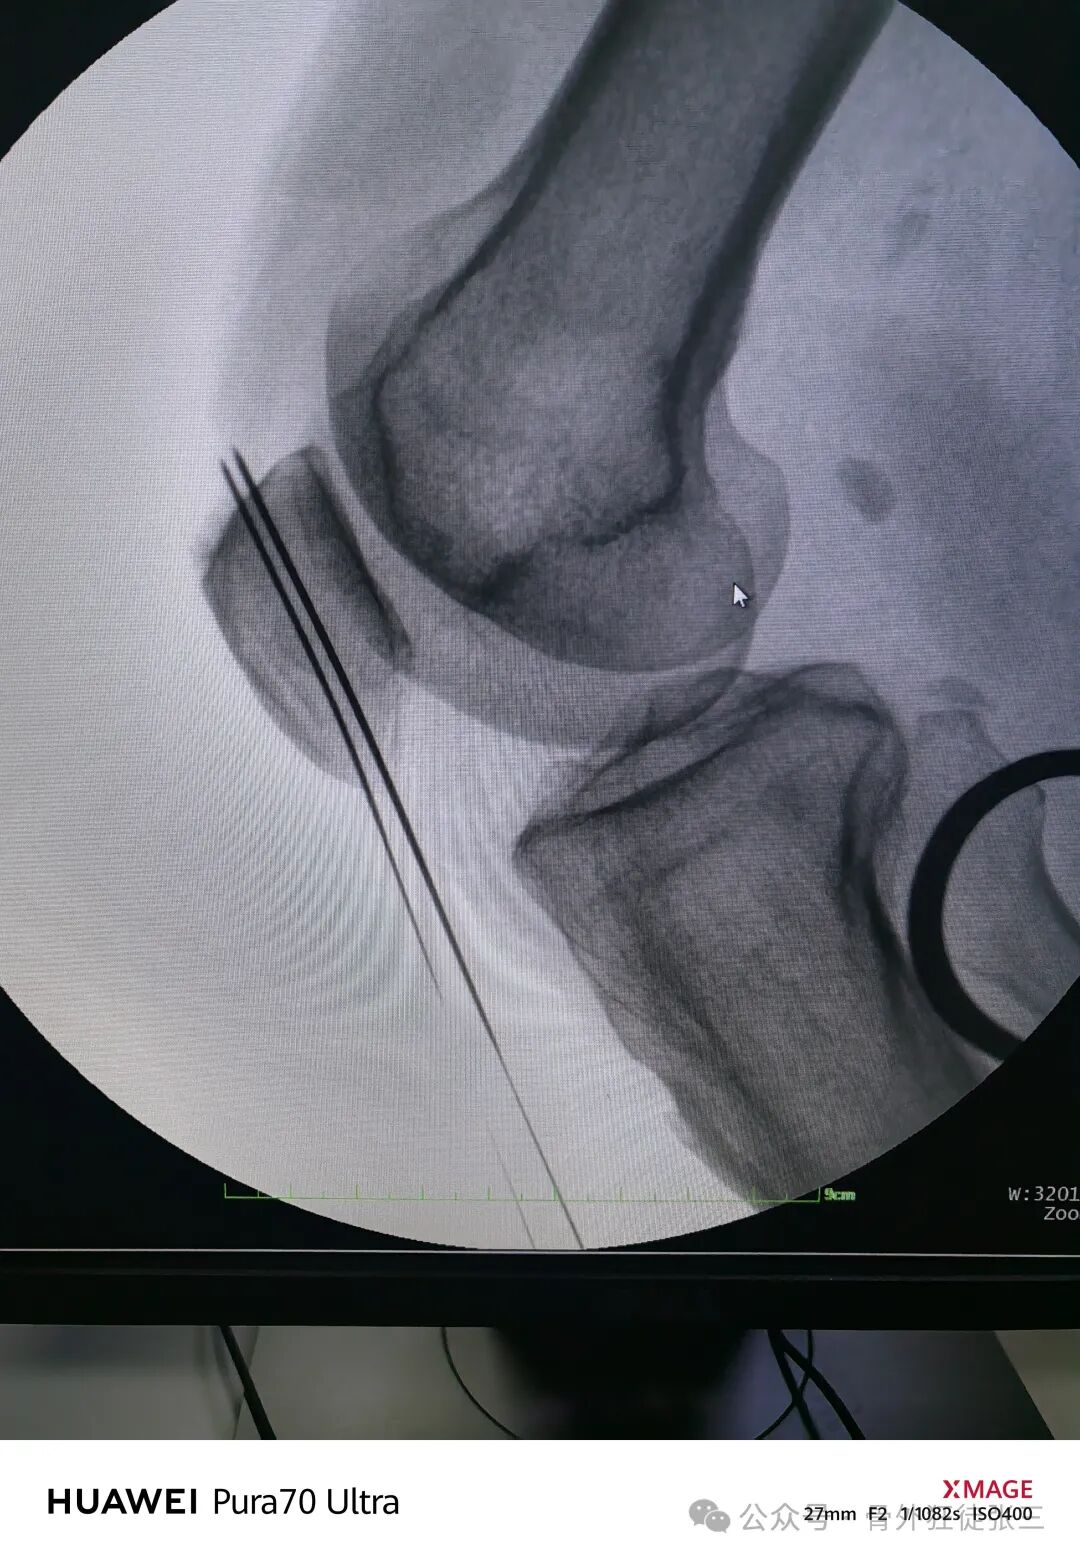

透视正位侧

-

打导针

空心钻钻孔后

如果张力大不好复位

可以经皮点式复位钳